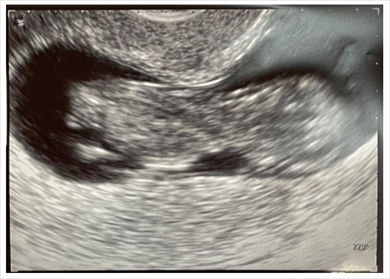

12日に妊婦健診を受けていただいたさんは、「一昨日のエコー写真の写りは、顔平ら疑惑が出てきました」と赤ちゃんの一部分が見えているエコー写真を公開。素人目では楕円形で起伏のない面だけが見えている状態のため“顔が平ら”だと心配になったようで、「背中と後頭部を見せていたと思いたいけれど…先生から、『目ですよ鼻ですよ』と言われても…えっ!? どこ!? と全然わからず」と医師から説明を受けている際の不安いっぱいな心境をつづっています。

だいたさんは、「でも、まだ分からないよね!? と自分を慰めています」とどうにか心を落ち着かせている様子。今回のエコーでは顔こそしっかり確認できませんでしたが、13日までのブログエントリーでは「心拍も逞しく5cmになっていました!」「はじめて動く姿も見れて 脚をバタバタ」「(心拍が)ドンドンドンドンと、リズム刻んでいました」など元気に成長している姿を確認できたことも明かしていました。

ブログ読者からは、「大きくなりましたね。順調ですね!」「着実にすくすく育っててほんとに嬉しいです」など前回のエコー写真よりも大きくなった赤ちゃんの姿に喜びの声があがった他、「エコー写真はわからないですよ、素人ですからね」「私もひかるさんと同じような感じで目も鼻もわかりませんでした なんとなく、頭と胴体がこれかな? みたいな」「病院の先生は見慣れてるので、顔のパーツもわかるのでしょうが、私も説明されても毎回、え? どれが鼻だって??? でしたね」などだいたさんの不安を解消してくれそうなコメントも届いています。